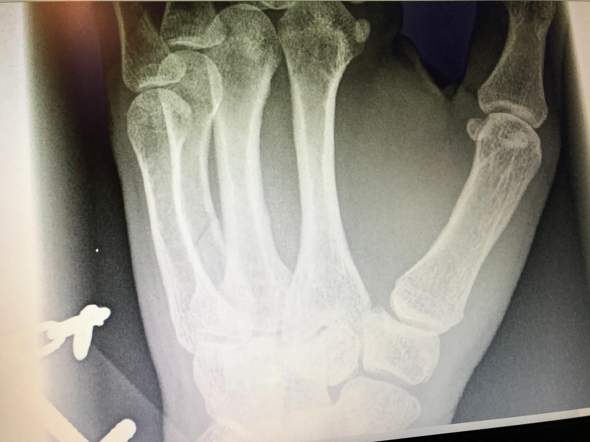

Mittelhandknochenbruch wie lange krank. Der Arzt hat mir einen Gips gemacht doch er hat mir nicht gesagt für wie lange. Dabei erhält der Patient für vier bis sechs Wochen eine Schiene aus Gips oder Kunststoff. Bei einem Bruch des 2.

Mittelhandfraktur Wie lange pause. Sie müssen dem Arbeitgeber zwar nicht sagen warum Sie erkrankt sind aber der Fairness halber sollten Sie ihm die Krankheitszeit mitteilen damit er sich darauf einstellen kann. Anschließend kann man von einer Heilung der Fraktur ausgehen die röntgenologisch bestätigt werden sollte.

Von Player 2 25 Feb 2010 2341 Hallo hatte im September auch zwei ueble Mittelhandfraktueren in der rechten Hand 2 OPs gehabt weil ich noch K Draehte die gezogen wurden im Knochenmark waren. Hier kannst du aber vieles positiv steuern.